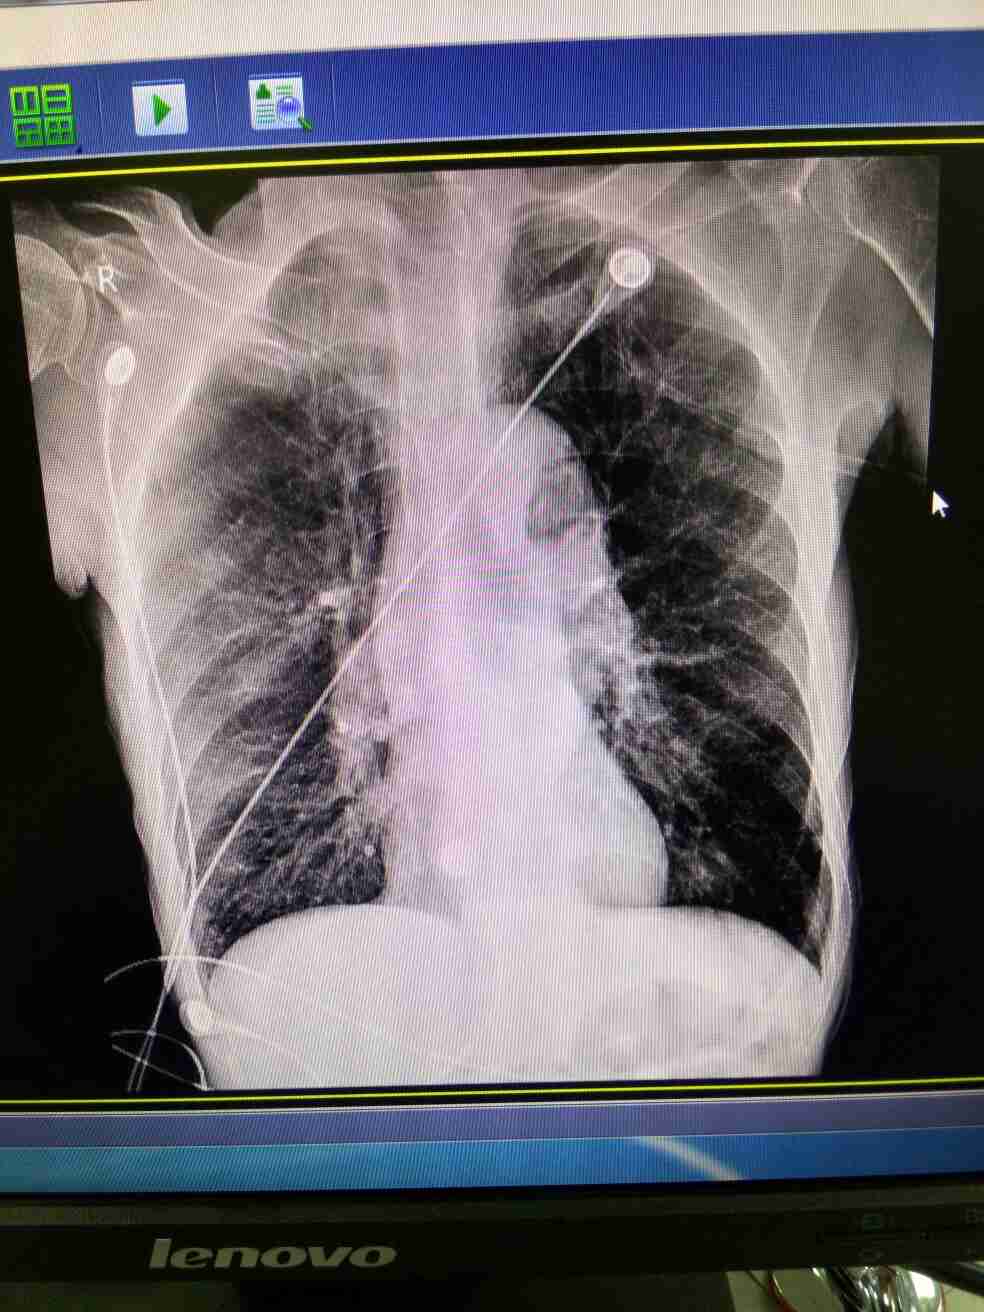

肺气肿 ( emphysema;pulmonary emphysema )